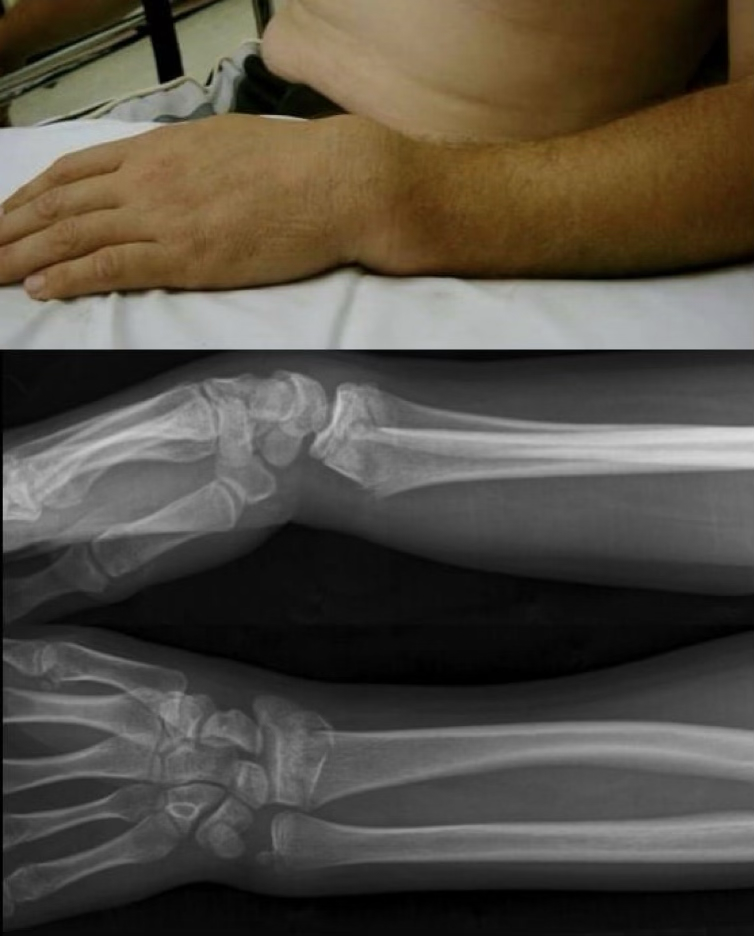

forearm fractures

FOOSH or direct blows

super common in youth due to the MOI, but rare to see it as ulanr and radial fractures simultaneously

Colles fx: radius & ulna fracture where they hyperextend (go dorsally)

smith fx: radius & ulna fracture and hyperflex (go volarly)

forearm fractures symptoms

pop, pain, swelling, possible deformity, lack of ROM

forearm fractures treatment

splint and ship, will need cast or surgery (4-8 weeks then therapy)